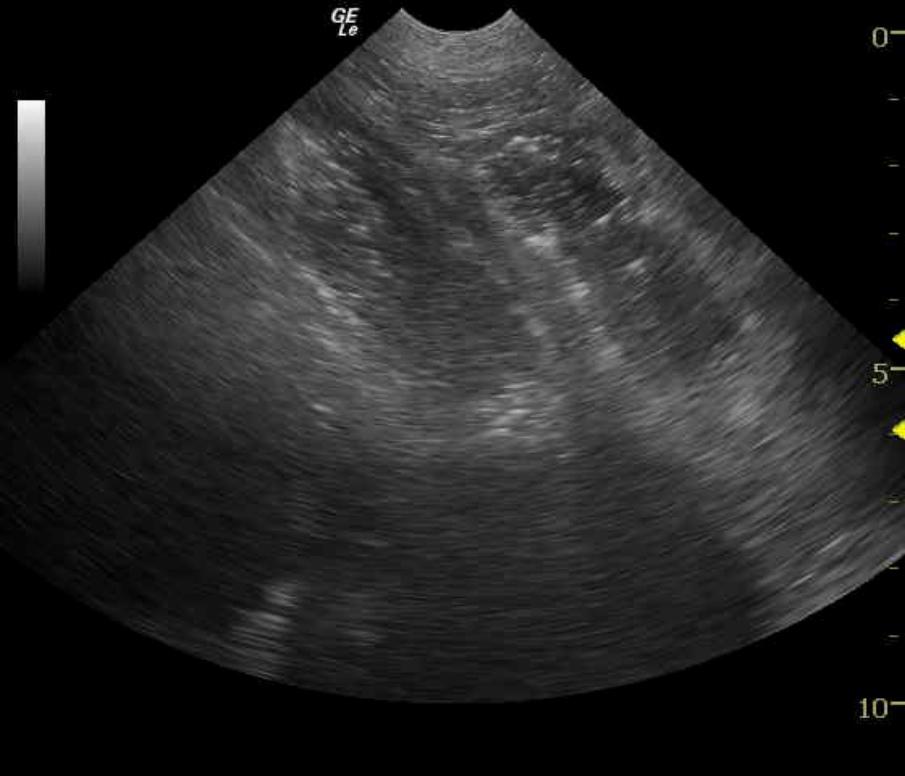

Obstructive intestinal pattern. Foreign body, focal dysfunctional bowel, occult neoplasia, enteritis.

Dilated small intestine is followed by echogenic, progressively shadowing intestinal artifact. Areas of empty small intestine are present, creating a sonographic pattern suggestive of an obstruction.